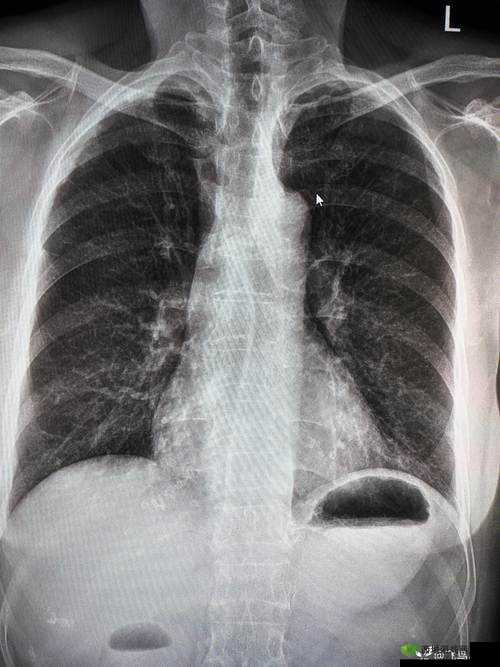

这组照片的创作者是一位资深的医学摄影师。他花费了大量时间和精力,通过特殊的技术手段,将胸片 100%曝光,从而揭示了情绪对人体的影响。在这些照片中,我们可以看到,在极度愤怒的情绪下,肺部的纹理变得异常清晰,甚至出现了明显的扭曲和变形。这是因为愤怒情绪会导致人体内分泌系统的变化,进而影响肺部的功能。